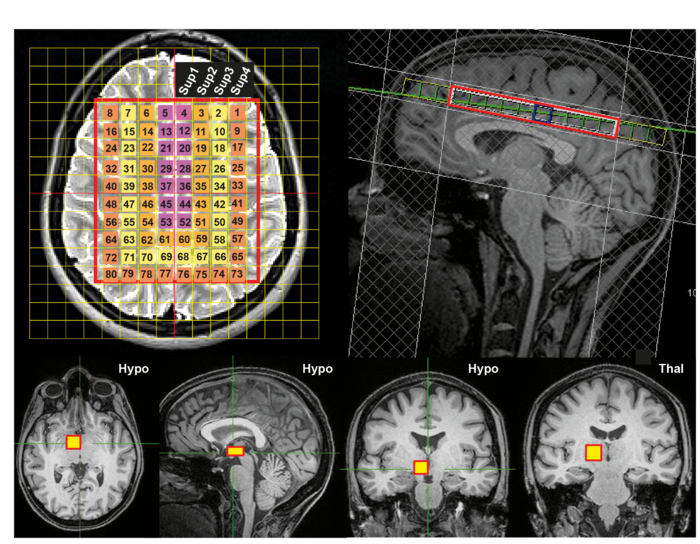

The new study, led by researchers at the Medical Research Council (MRC) Laboratory for Molecular Biology, in Cambridge, UK, has produced the first 4D map of healthy human brain temperature. This map overturns several previous assumptions and shows the remarkable extent to which brain temperature varies by brain region, age, sex, and time of day. Importantly, these findings also challenge a widely held belief that human brain and body temperature are the same.

“Using the most comprehensive exploration to date of normal human brain temperature, we’ve established ‘ HEATWAVE ’ - a 4D temperature map of the brain. This map provides an urgently-needed reference resource against which patient data can be compared, and could transform our understanding of how the brain works. That a daily brain temperature rhythm correlates so strongly with survival after TBI suggests that round-the-clock brain temperature measurement holds great clinical value.”